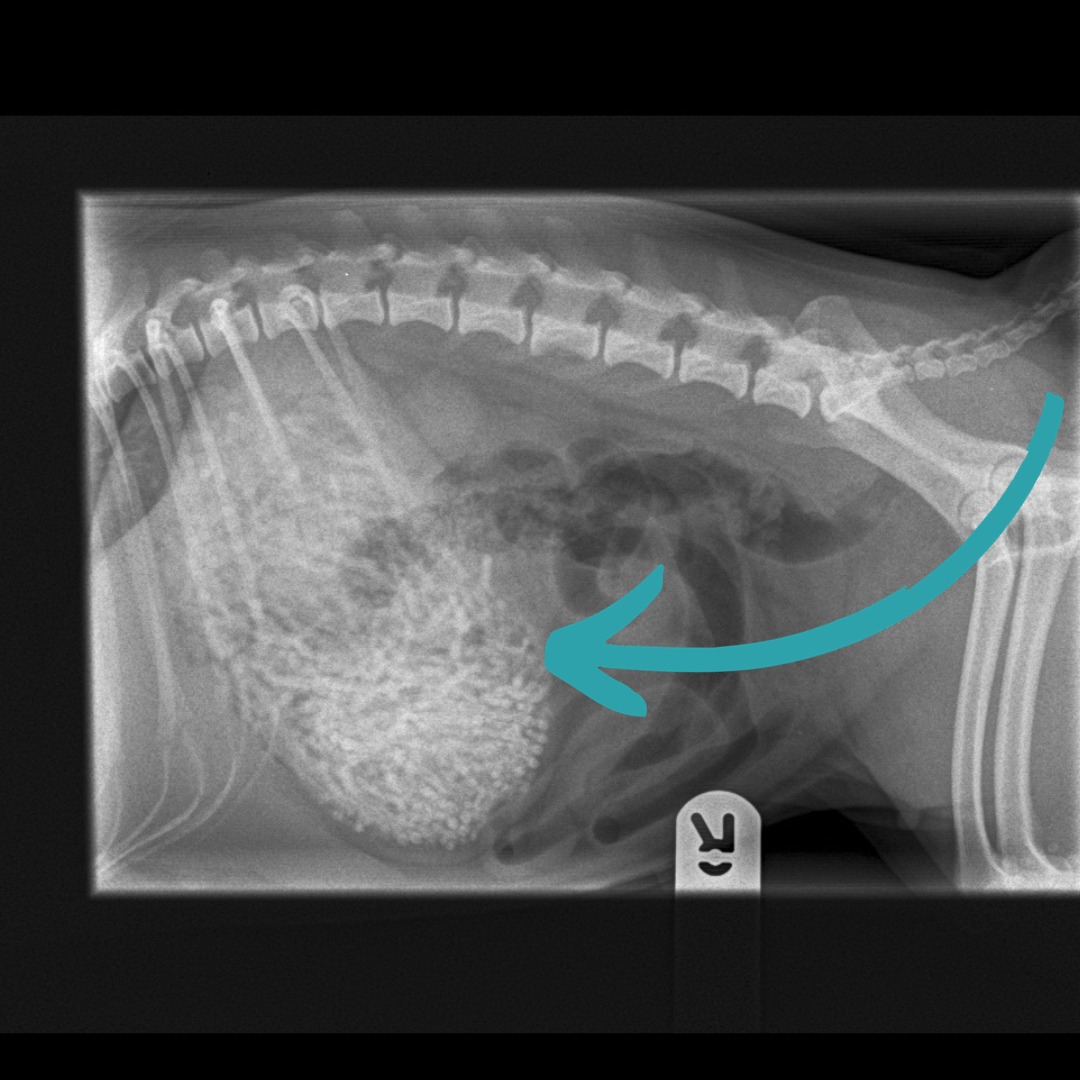

Prva preiskava veterinarske ordinacije Newton Clarke je pokazala, da je psička v želodcu imela nekaj nenavadnega, zato so se nemudoma odločili za operacijo.

Veterinarka Emily Whitby je povedala, da so odstranili od 50 do 60 gumic, ki so tehtale 200 gramov – Ham ima le šest kilogramov.